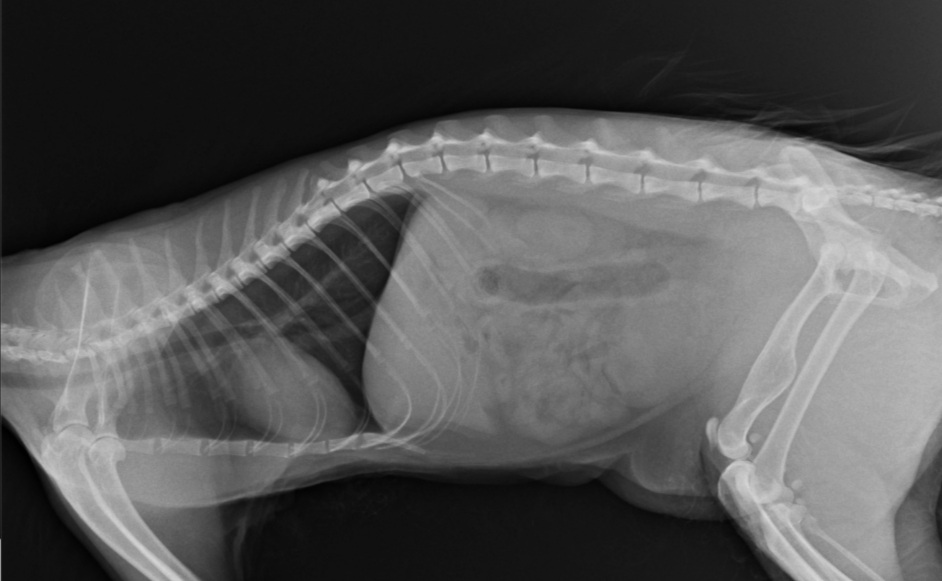

Trzy lata temu odłowiłam na osiedlu do sterylizacji dziką około 2letnią kotkę, która nazwaliśmy LUSI. Okazało się, że ma gorączkę, zapalenie płuc i inne przypadłości kota dziko - żyjącego. Z uwagi na konieczność leczenia, LUSIA zamieszkała z nami. Bardzo szybko zaadoptowała się do nowych warunków, więc została z nami. W tym roku zrealizowałam moje marzenie i przeprowadziłam się do mieszkania z ogródkiem. W trakcie prac wykończeniowych, przez nieuwagę pracownika wystraszona uciekła. Blisko 3 miesiące poszukiwałam ją bezskutecznie, aż do 18 marca Tego dnia szłam do domu i kotka słysząc mój głos, wyczołgała się z krzaków pod moje nogi ciągnąc za sobą tylną łapkę. Od razu udałam się do weterynarza i cios w serce... Okazało się, że LUSI została brutalnie, z wielką siłą potrącona przez samochód kilka tygodni wcześniej i pozostawiona w olbrzymim bólu i cierpieniu. Kotka po tym zdarzeniu zdziczała, ale nie dając za wygraną udałam się do znanego i polecanego specjalisty chirurga – ortopedy. Weterynarz zaleciła dalszą diagnostykę neurologiczną, leczenie farmakologiczne i dała nadzieję na wyzdrowienie kotki po zoperowaniu jej pękniętej miednicy i łapki. Niestety z uwagi na trudną sytuację finansową, nie jestem w stanie sama podołać tym kosztom. Bardzo proszę o wsparcie, abym mogła ulżyć kotce w cierpieniu.